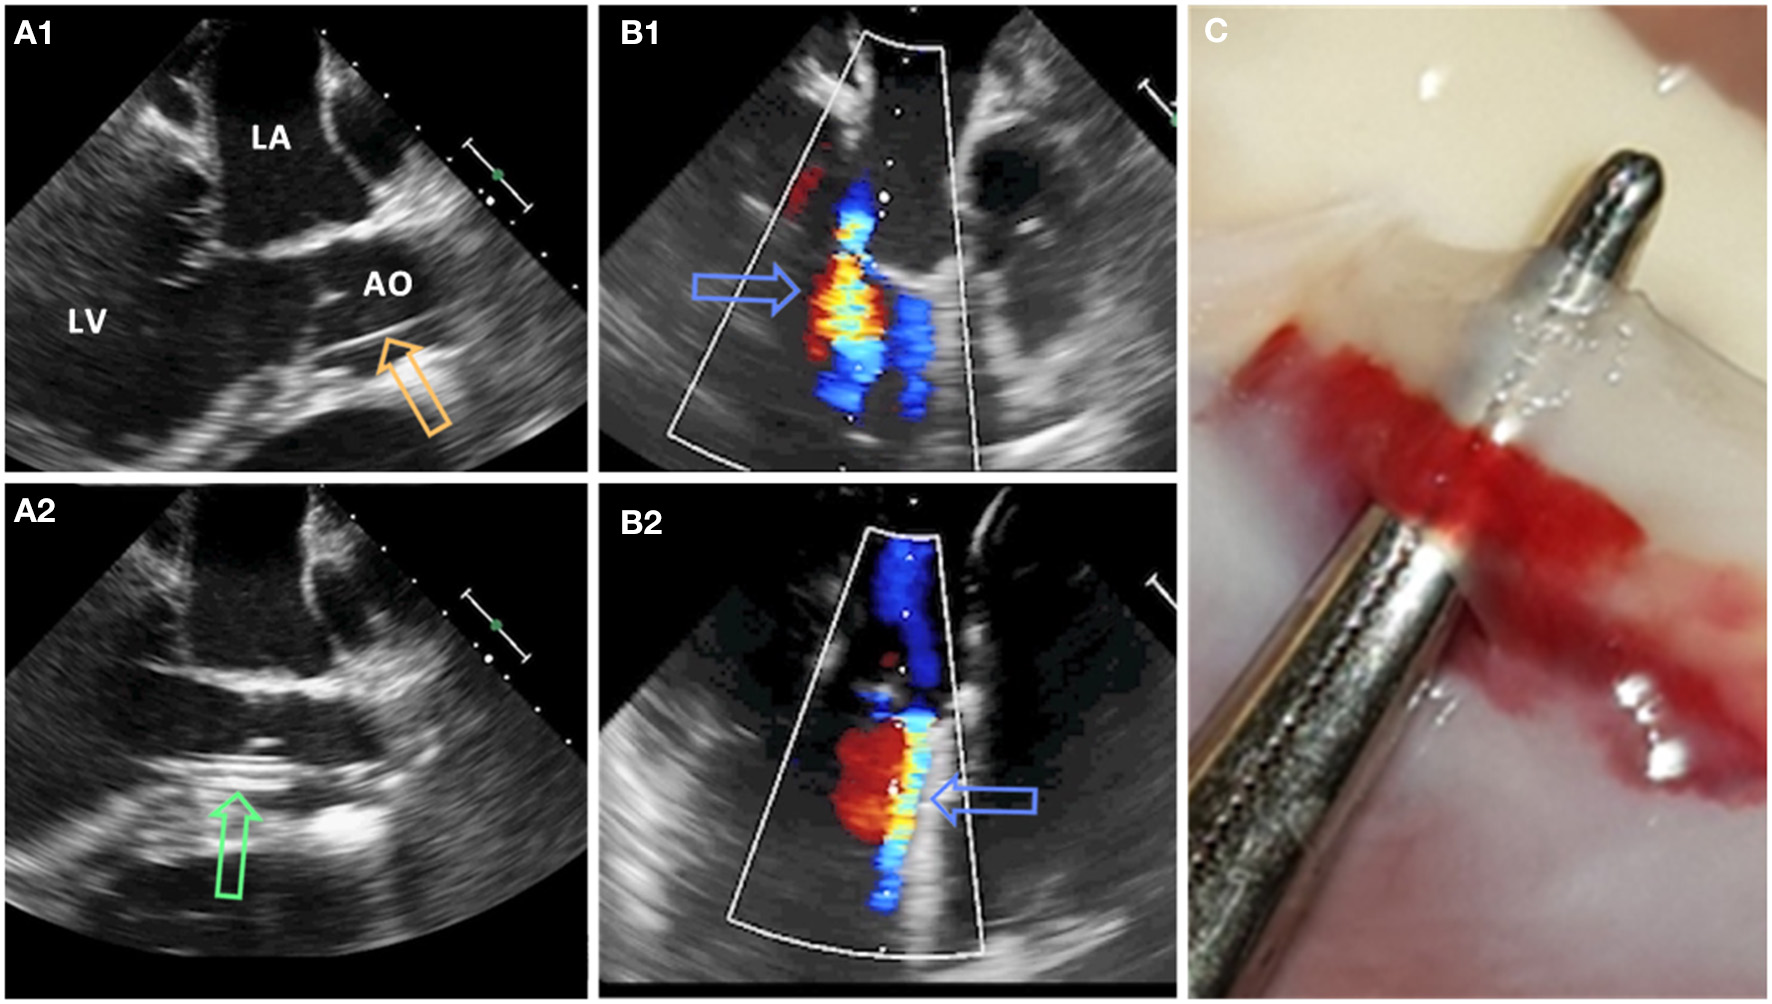

At the beginning of the experiment, all animals received premedication with ketamine (20 mg/kg), azaperone (1.5 mg/kg), and atropine (0.75 mg) intramuscularly. After loss of postural reflexes, the anesthesia was deepened by a bolus injection of propofol (1–2 mg/kg) to facilitate intubation. Anesthesia maintained with 2–3% isoflurane and propofol (2–5 mg/kg/h) for the remainder of the experiment. Amiodarone (2–3 mg/kg bolus iv) was administered to stabilize the heart rhythm. Pain management included fentanyl infusion (0.02 mg/kg/h) for the duration of the procedure. Aortic valve defects were induced with transcatheter approach by a pierce and dilate technique at the hinge points of the NCC or the RCC, respectively. Due to its symmetrical position as NCC in respect to the mitral valve, close proximity of the orifice of the left coronary artery and potential life threatening complications if partially occluded during the intervention, left coronary cusp (LCC) defect was omitted in this study. In brief, the target point in the NCC or RCC was reached under Echo and Fluoroscopy guidance by using a steerable sheet (Agilis™ EPI Steerable Sheath, 8.5F, St. Jude Medical, Minnetonka, MN, USA). The annulus/leaflet hinge was pierced with a stiff-end of a coronary guide-wire (IRON MAN Guide Wire, 0.014″ 190 cm, Abbott Vascular, Santa Clara CA, USA). The puncture was then dilated with a 5 mm PTCA balloon (NC Emerge MONORAIL™ PTCA Dilation Balloon 5 x 12 mm, Boston Scientific Corporation, Marlborough, MA, USA) (Figure 1). Due to the elasticity of non-calcified annular and leaflet tissue, defects have been expected to reduce the size uniformly in all animals. Hence, the effective regurgitant orifice was expected to be smaller than the 5 mm balloon used for dilatation.

Figure 1

Pierce and dilate technique used to create the model of mild eccentric aortic regurgitation/para valvular leakage (AO, aorta; LA, left atrium; LV, left ventricle). (A1) Coronary guide wire (orange arrow) is used to pierce the leaflet/annulus at the hinge point. (A2) Standard PTCA 5 mm balloon (green arrow) is positioned across the defect and inflated. (B1,B2) Aortic regurgitant jet (blue arrows) originating from NCC and RCC region, respectively. (C) Defect of the aortic valve at the hinge point of the leaflet.